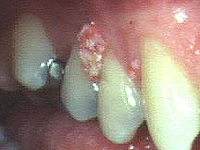

口腔菜花